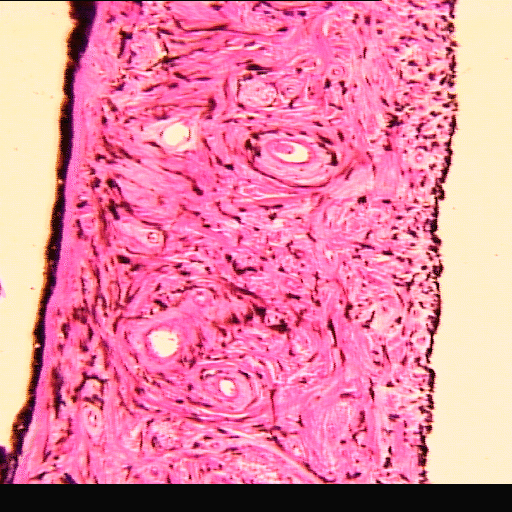

(EN) : Longitudinal section of the iris from an ox (Hematoxylin and eosin stain (H&E), x10, Slide RCB-45 P3.2).

(FR) : Coupe longitudinale de l'iris d'un bœuf (coloration à l'hématoxyline et à l'éosine (H&E), x10, Lame RBC-45 P3.2).